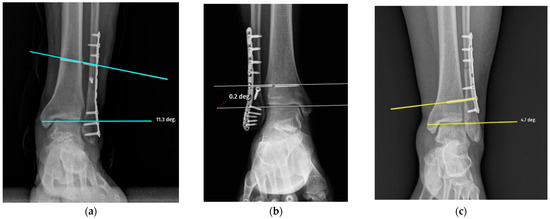

Radiographic and Demographic Factors Associated with Syndesmotic Screw Breakage in Ankle Fractures

by Emre Kocazeybek, Mehmet Ekinci, Salih Magi, Murat Altunsoy, Kubilay Yolaçan, Murat Yılmaz and Mehmet Ersin

J. Clin. Med. 2026, 15(7), 2647; https://doi.org/10.3390/jcm15072647 - 31 Mar 2026

Background: Syndesmotic screw breakage is a well-recognized mechanical complication following ankle fracture fixation. Although several studies have investigated patient-related and technical factors associated with screw breakage, the temporal pattern of screw failure and implant survival remains less clearly defined. Therefore, this study aimed [...] Read more.

Background: Syndesmotic screw breakage is a well-recognized mechanical complication following ankle fracture fixation. Although several studies have investigated patient-related and technical factors associated with screw breakage, the temporal pattern of screw failure and implant survival remains less clearly defined. Therefore, this study aimed to evaluate one-year syndesmotic screw survival using time-to-event analysis and to identify factors associated with screw breakage. Materials and Methods: A total of 132 patients with unstable AO-Weber 44-B/C ankle fractures treated with syndesmotic screw fixation were retrospectively analyzed. Patients were followed for a minimum of 12 months or until screw breakage occurred. Screw survival was evaluated using Kaplan–Meier analysis and Cox proportional hazards regression was performed to identify factors associated with screw breakage. Demographic variables, fracture type, and screw-related parameters were analyzed. Receiver operating characteristic (ROC) analysis was used to assess the discriminative ability of age. Results: Screw breakage occurred in 31 patients (23.5%) during follow-up. Kaplan–Meier analysis demonstrated significantly lower screw survival in Weber C fractures compared with Weber B fractures (log-rank p < 0.001). Cox regression analysis identified younger age (HR: 0.965, 95% CI: 0.937–0.993, p = 0.016) and Weber C fracture type (HR: 1.811, 95% CI: 1.260–2.602, p = 0.001) as independent predictors of screw breakage. ROC analysis showed that age had moderate discriminative ability (AUC: 0.719, 95% CI: 0.612–0.816), with a cut-off value of 35.5 years. Conclusions: Younger age and Weber C fracture type are associated with an increased risk of syndesmotic screw breakage and Weber C fractures also demonstrating reduced screw survival. These findings may assist in patient counseling; however, the clinical implications of screw breakage remain uncertain. Full article